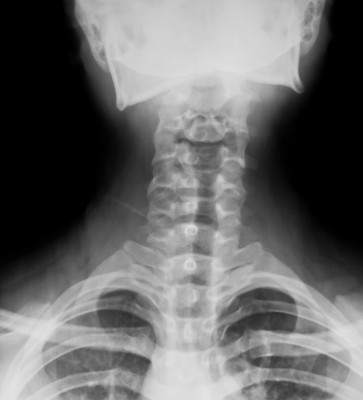

Role of X-Rays in Chiropractic X-rays (or diagnostic images) play a vital role in Chiropractic. They allow If your chiropractor owns x-ray equipment, the machine must be inspected regularly and meet the standards of the National ... Return Document

Commentary Chiropractors’ Use Of X-rays